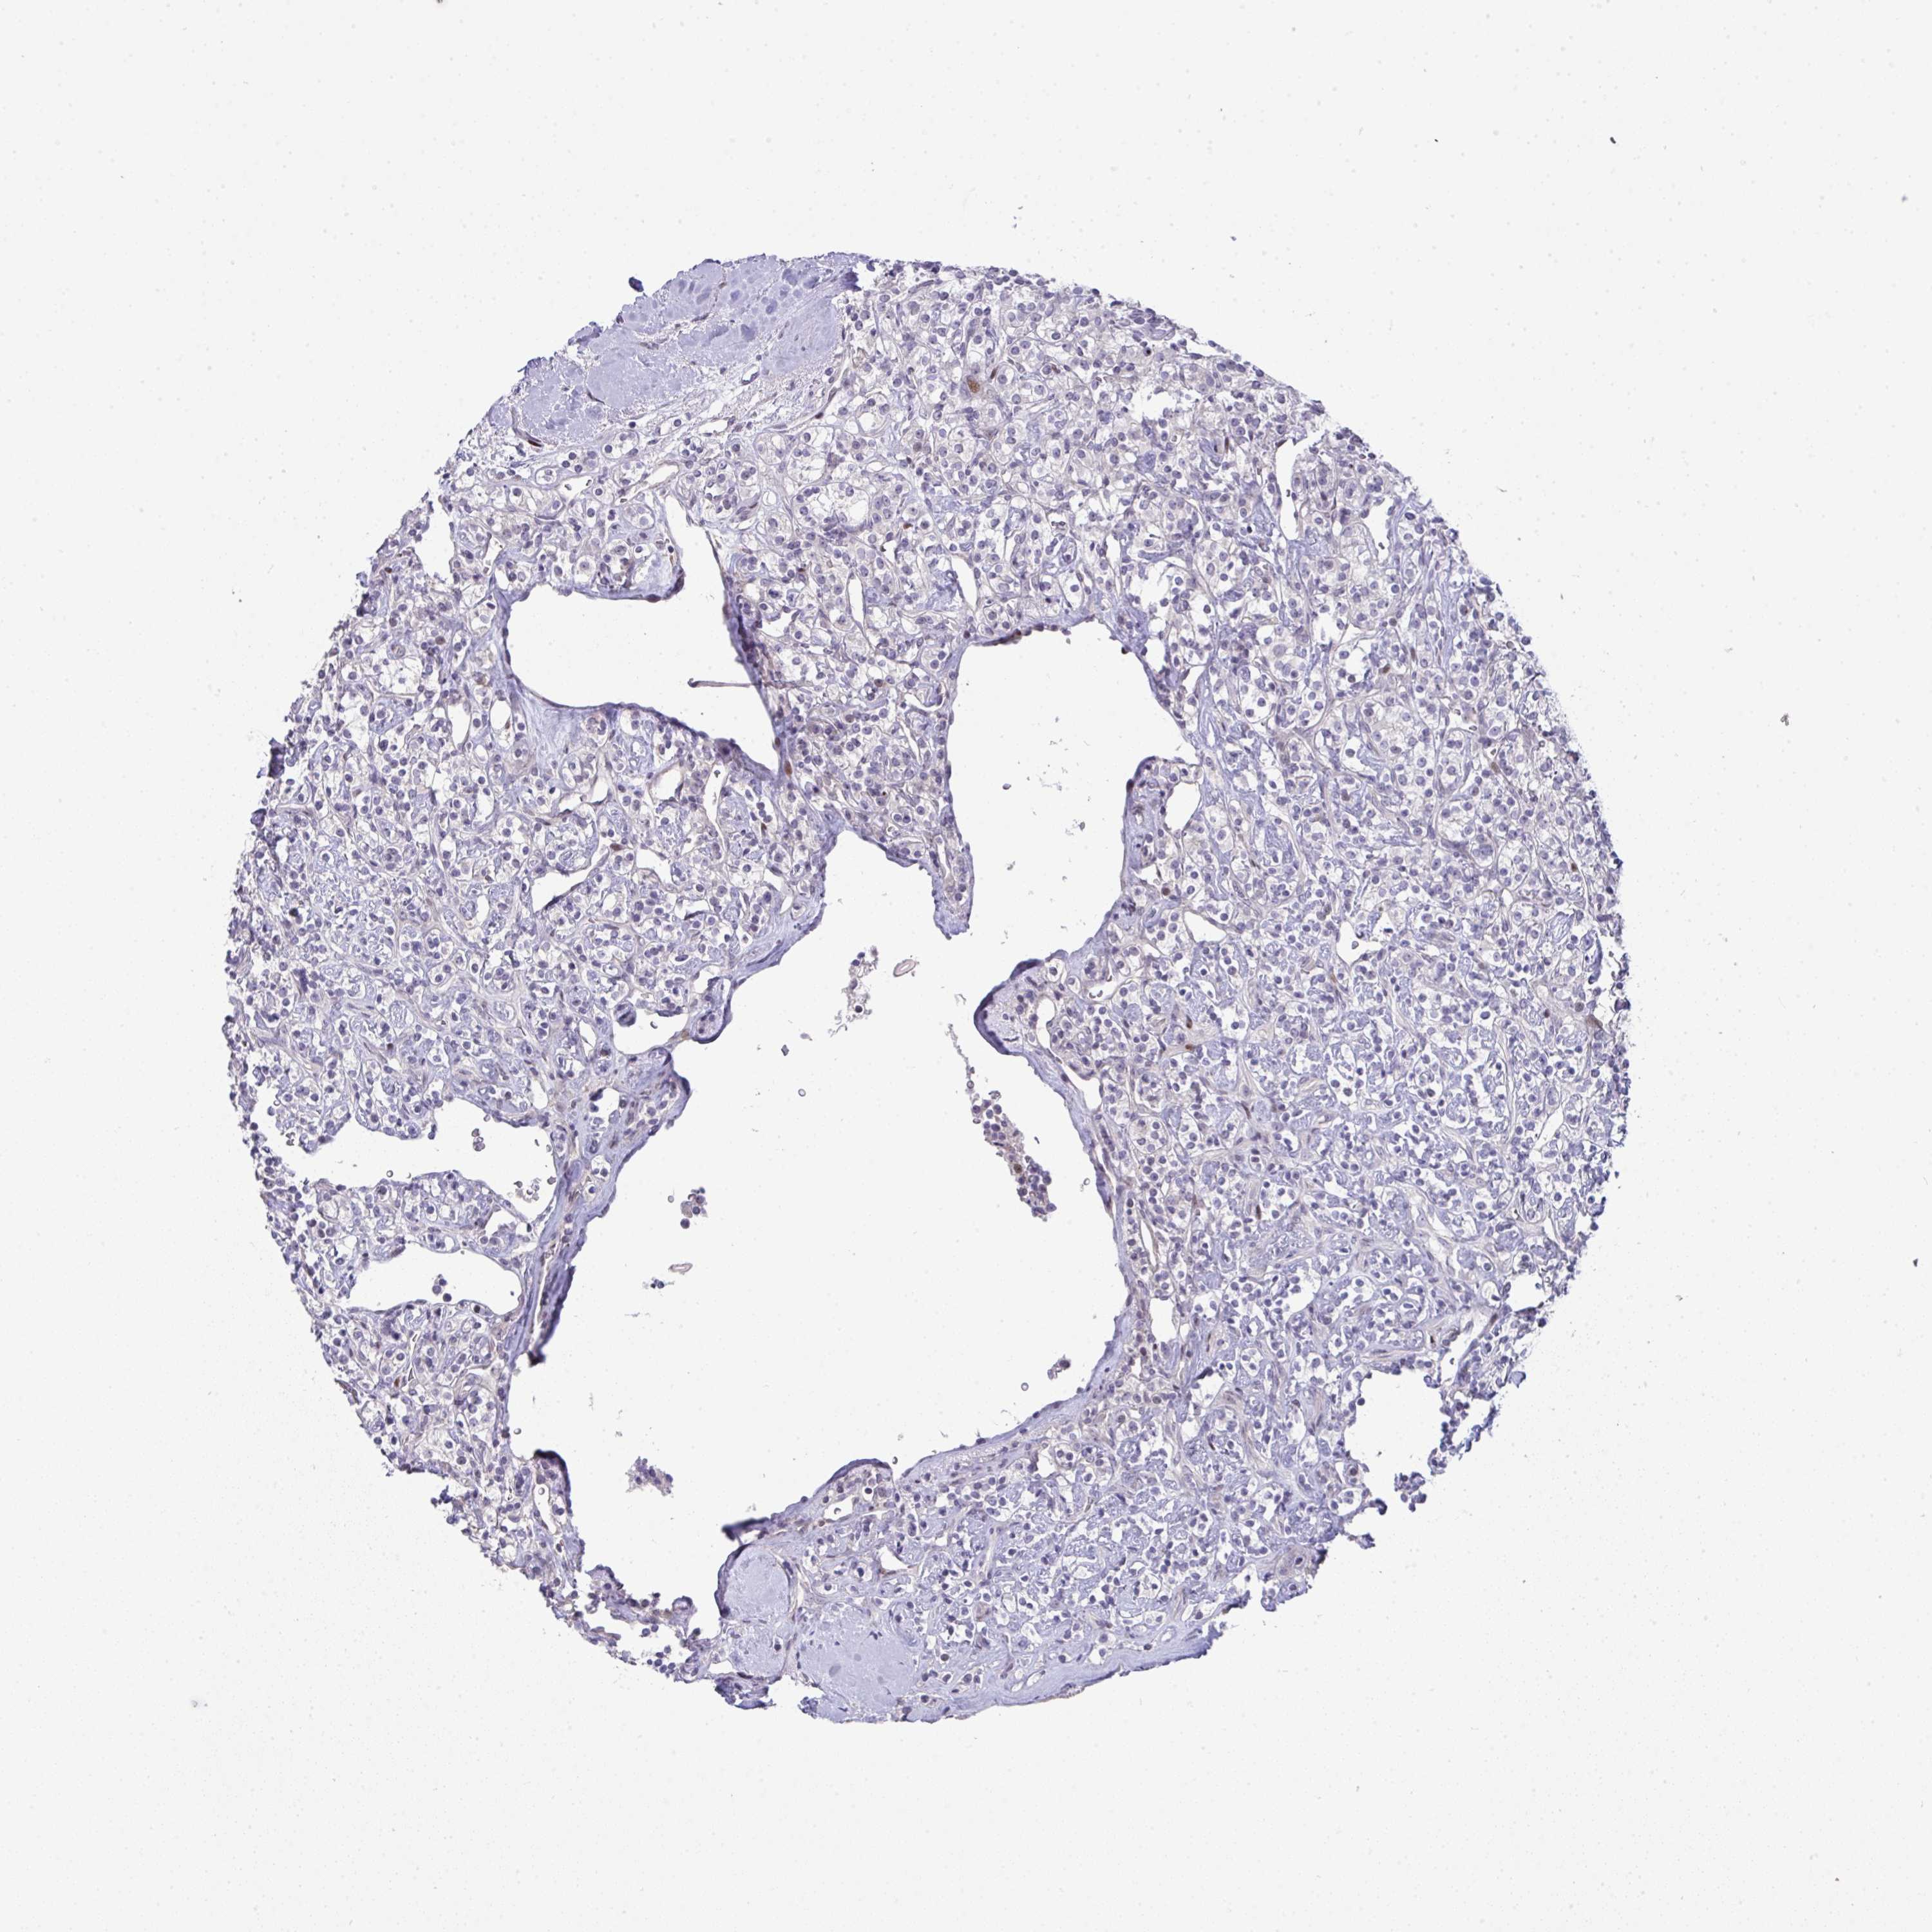

KIDNEY RENAL CLEAR CELL CARCINOMA (VALIDATION) - Interactive survival scatter ploti

The Survival Scatter plot shows the clinical status (i.e. dead or alive) for all individuals in the patient cohort, based on the same data that underlies the corresponding Kaplan-Meier plots. Patients that are alive at last time for follow-up are shown in blue and patients who have died during the study are shown in red.

The x-axis shows the expression levels (FPKM) of the investigated gene in the tumor tissue at the time of diagnosis. The y-axis shows the follow-up time after diagnosis (years). Both axes are complimented with kernel density curves demonstrating the data density over the axes. The top density plot shows the expression levels (FPKM) distribution among dead (red) and alive patients (blue). The right density plot shows the data density of the survived years of dead patients with high and low expression levels respectively, stratified using the cutoff indicated by the vertical dashed line through the Survival Scatter plot. This cutoff is automatically defined based on the FPKM cutoff that minimizes the p-score. The cutoff can be changed by dragging the vertical line or by entering a cutoff value in the square labeled "Current cut-off".

Under the Survival Scatter plot the p-score landscape (black curve; left axis) is shown together with dead median separation (red curve; right axis). Dead median separation is the difference in median mRNA expression between patients who have died with high and low expression, respectively. It is calculated as follows: median FPKM expression of dead patients with high expression - median FPKM expression of dead patients with low expression. This is intended to aid the user in visually exploring custom cutoffs and the associated p-scores and dead median separation.

Individual patient data is displayed and can be filtered by clicking on one or more of the category buttons on the top of the page. Categories describing expression level and patient information include: high, low, alive, dead, female, male and tumor stages. The scale of the x-axis can be toggled between linear and log-scale by clicking on the "x log" button. Mouse-over function shows TCGA ID, patient information and mRNA expression (FPKM) for each patient.

& Survival analysisi

Kaplan-Meier plots summarize results from analysis of correlation between mRNA expression level and patient survival. Patients were divided based on level of expression into one of the two groups "low" (under cut off) or "high" (over cut off). X-axis shows time for survival (years) and y-axis shows the probability of survival, where 1.0 corresponds to 100 percent.

GALNT16 is not prognostic in Kidney Renal Clear Cell Carcinoma (validation)

Best expression cut offi

Based on the FPKM value of each gene, patients were classified into two groups and association between prognosis (survival) and gene expression (FPKM) was examined. The best expression cut-off refers the FPKM value that yields maximal difference with regard to survival between the two groups at the lowest log-rank P-value. Best expression cut-off was selected based on survival analysis .

When clicking on this number, the vertical dashed line indicating cut-off, the interactive survival plot, and the Kaplan-Meier curve will be adjusted to show results based on the best expression cut-off.

: 0.58

P scorei

Log-rank P value for Kaplan-Meier plot showing results from analysis of correlation between mRNA expression level and patient survival.

N/A

TCGA RNA samplesi

RNA-seq data is reported as average FPKM (number Fragments Per Kilobase of exon per Million reads), generated by the The Cancer Genome Atlas (TCGA) .

Normal distribution across the dataset is visualized with box plots, shown as median and 25th and 75th percentiles. Points are displayed as outliers if they are above or below 1.5 times the interquartile range. FPKM values of the individual samples are presented next to the box plot.

Average pTPM 2.0

Number of samples 100